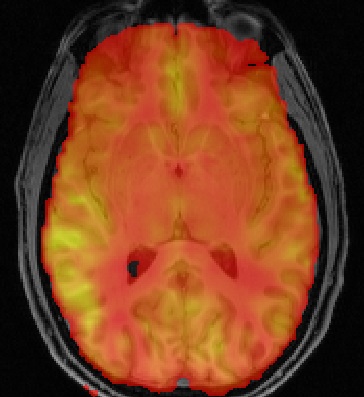

Arterial Spin Labeling (ASL) MRI is a non-invasive method for the quantification of perfusion. Analysis of ASL data typically requires the inversion of a kinetic model of label inflow along with a separate calculation of the equilibrium magnetization of arterial blood. The BASIL toolbox provides a means to do this based on Bayeisan inference principles. The method was orginally developed for multi delay (inversion time) data where it can be used to greatest effect, but is also sufficiently fleixble to deal with the widely used single delay form of acquisition.